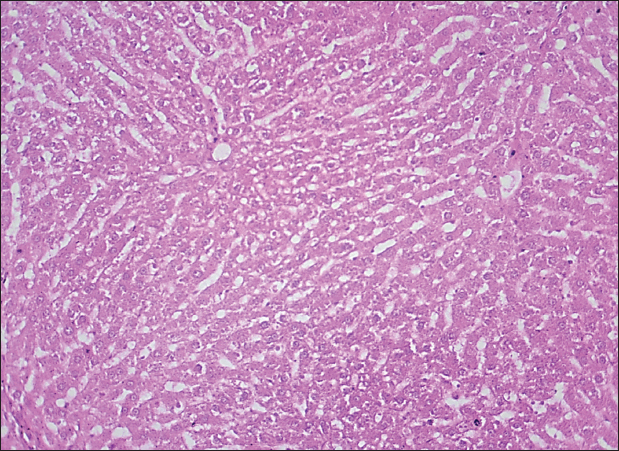

The results of this study revealed no significant differences in bilirubin levels in all treated animals (Table 1), whereas serum ALT and AST levels showed significant elevations in all treated animals either by citalopram alone (fourth group) or with J. regia pulp extract at doses of both 10 and 20 mg/kg (Tables 2 and 3). Sections of histopathological study appeared as mild degenerative lesions characterized by infiltration of fat droplets inside hepatic cells, which gave them a ring shape appearance due to pushing the nucleus at one side from the hepatic cells with fibrous networks formation in the tissue parenchyma, infiltration of structureless, homogenous, and pinkish material (Figs. 16). Clear hepatic vein congestion and narrowing in the hepatic artery and arteriole diameters revealed that citalopram caused liver dysfunction and injury (Figs. 79).

These results correspond with those of other studies, in which patients treated with antidepressants appeared to have moderately elevated levels of the aminotransferase. All antidepressants caused hepatotoxicity; citalopram is that have the least potential for hepatotoxicity, which is characterized by high alanine aminotransferase levels (Gartlehner et al., 2008; Voican et al., 2014; Ilgın et al., 2020). The results of this study revealed no significant differences in bilirubin levels in all treated animals as the level of p < 0.05, serum ALT and AST levels showed a significant elevation in all treated animals either by citalopram only (fourth group) or with J. regia pulp extract at doses of 10 and 20 mg/kg B.W. Sections of histopathological sections show mild degenerative lesions characterized by infiltration of fat droplets inside hepatic cells, which give them a ring shape appearance due to pushing the nucleus at one side from the hepatic cells with fibrous networks formation in the tissue parenchyma, infiltration of structureless, homogenous, and pinkish material (Figs. 4 and 6). Clear hepatic vein congestion and narrowing in the hepatic artery and arteriole diameters revealed that citalopram caused liver dysfunction and injury (Figs. 79).

Fig. 4. Histological section of the liver of rats drenched with 0.6 mg/kg citalopram. The section shows a mild degenerative lesion (fatty degeneration, black arrows) with fibrous network formation in parenchyma (red arrow), (H and E stain 100X).